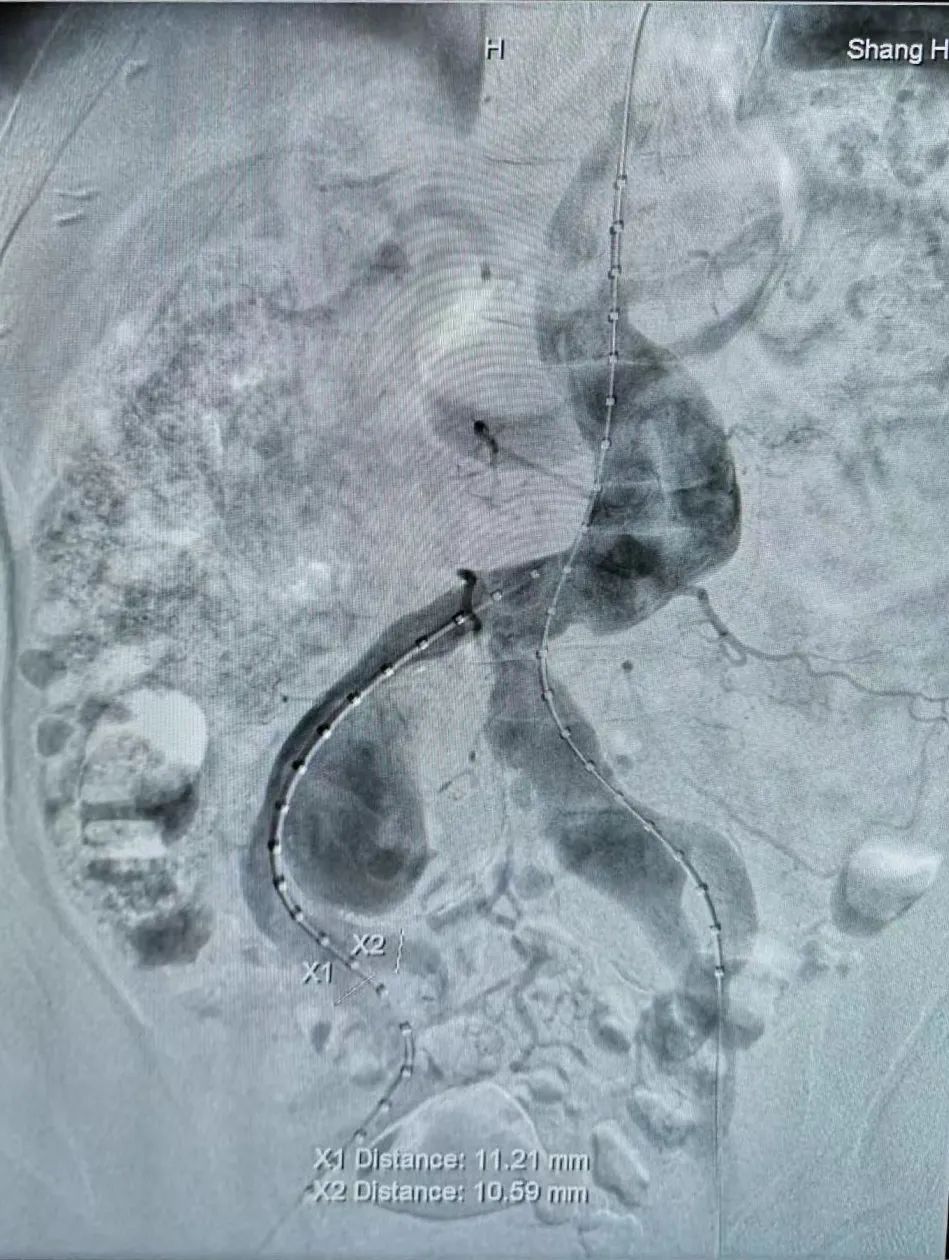

目前,针对腹主动脉瘤腔内治疗保留或重建髂内动脉的方法有很多,如“三明治”、“喇叭腿”、髂内分支支架IBD技术等。薛冠华经过缜密思考,为许先生制定了一期行“三明治”技术隔绝较大一侧髂动脉瘤并重建髂内动脉,较小一侧髂动脉瘤使用“喇叭腿”技术隔绝瘤体同时保留髂内动脉,如瘤体仍持续增大,则二期使用髂内分支支架IBD技术重建髂内动脉的手术方案。这个方案既兼顾了手术的微创性、技术的合理性、支架的长期通畅性,又充分考虑了患者对手术的耐受度。许先生对手术方案欣然接受。

薛冠华带领主治医师杨硕菲等按照既定计划,术中克服巨大瘤体超选困难、扭曲血管器械推送困难、狭窄血管支架通过困难等一系列技术难点,经过分期手术,成功拆除巨大腹主动脉瘤合并双髂动脉瘤,既完全隔绝了动脉瘤,又重建了两侧髂内动脉。许先生恢复顺利,术后24小时便可下床活动。出院时,许先生对附属仁济医院血管外科的精湛技术竖起大拇指“点赞”。